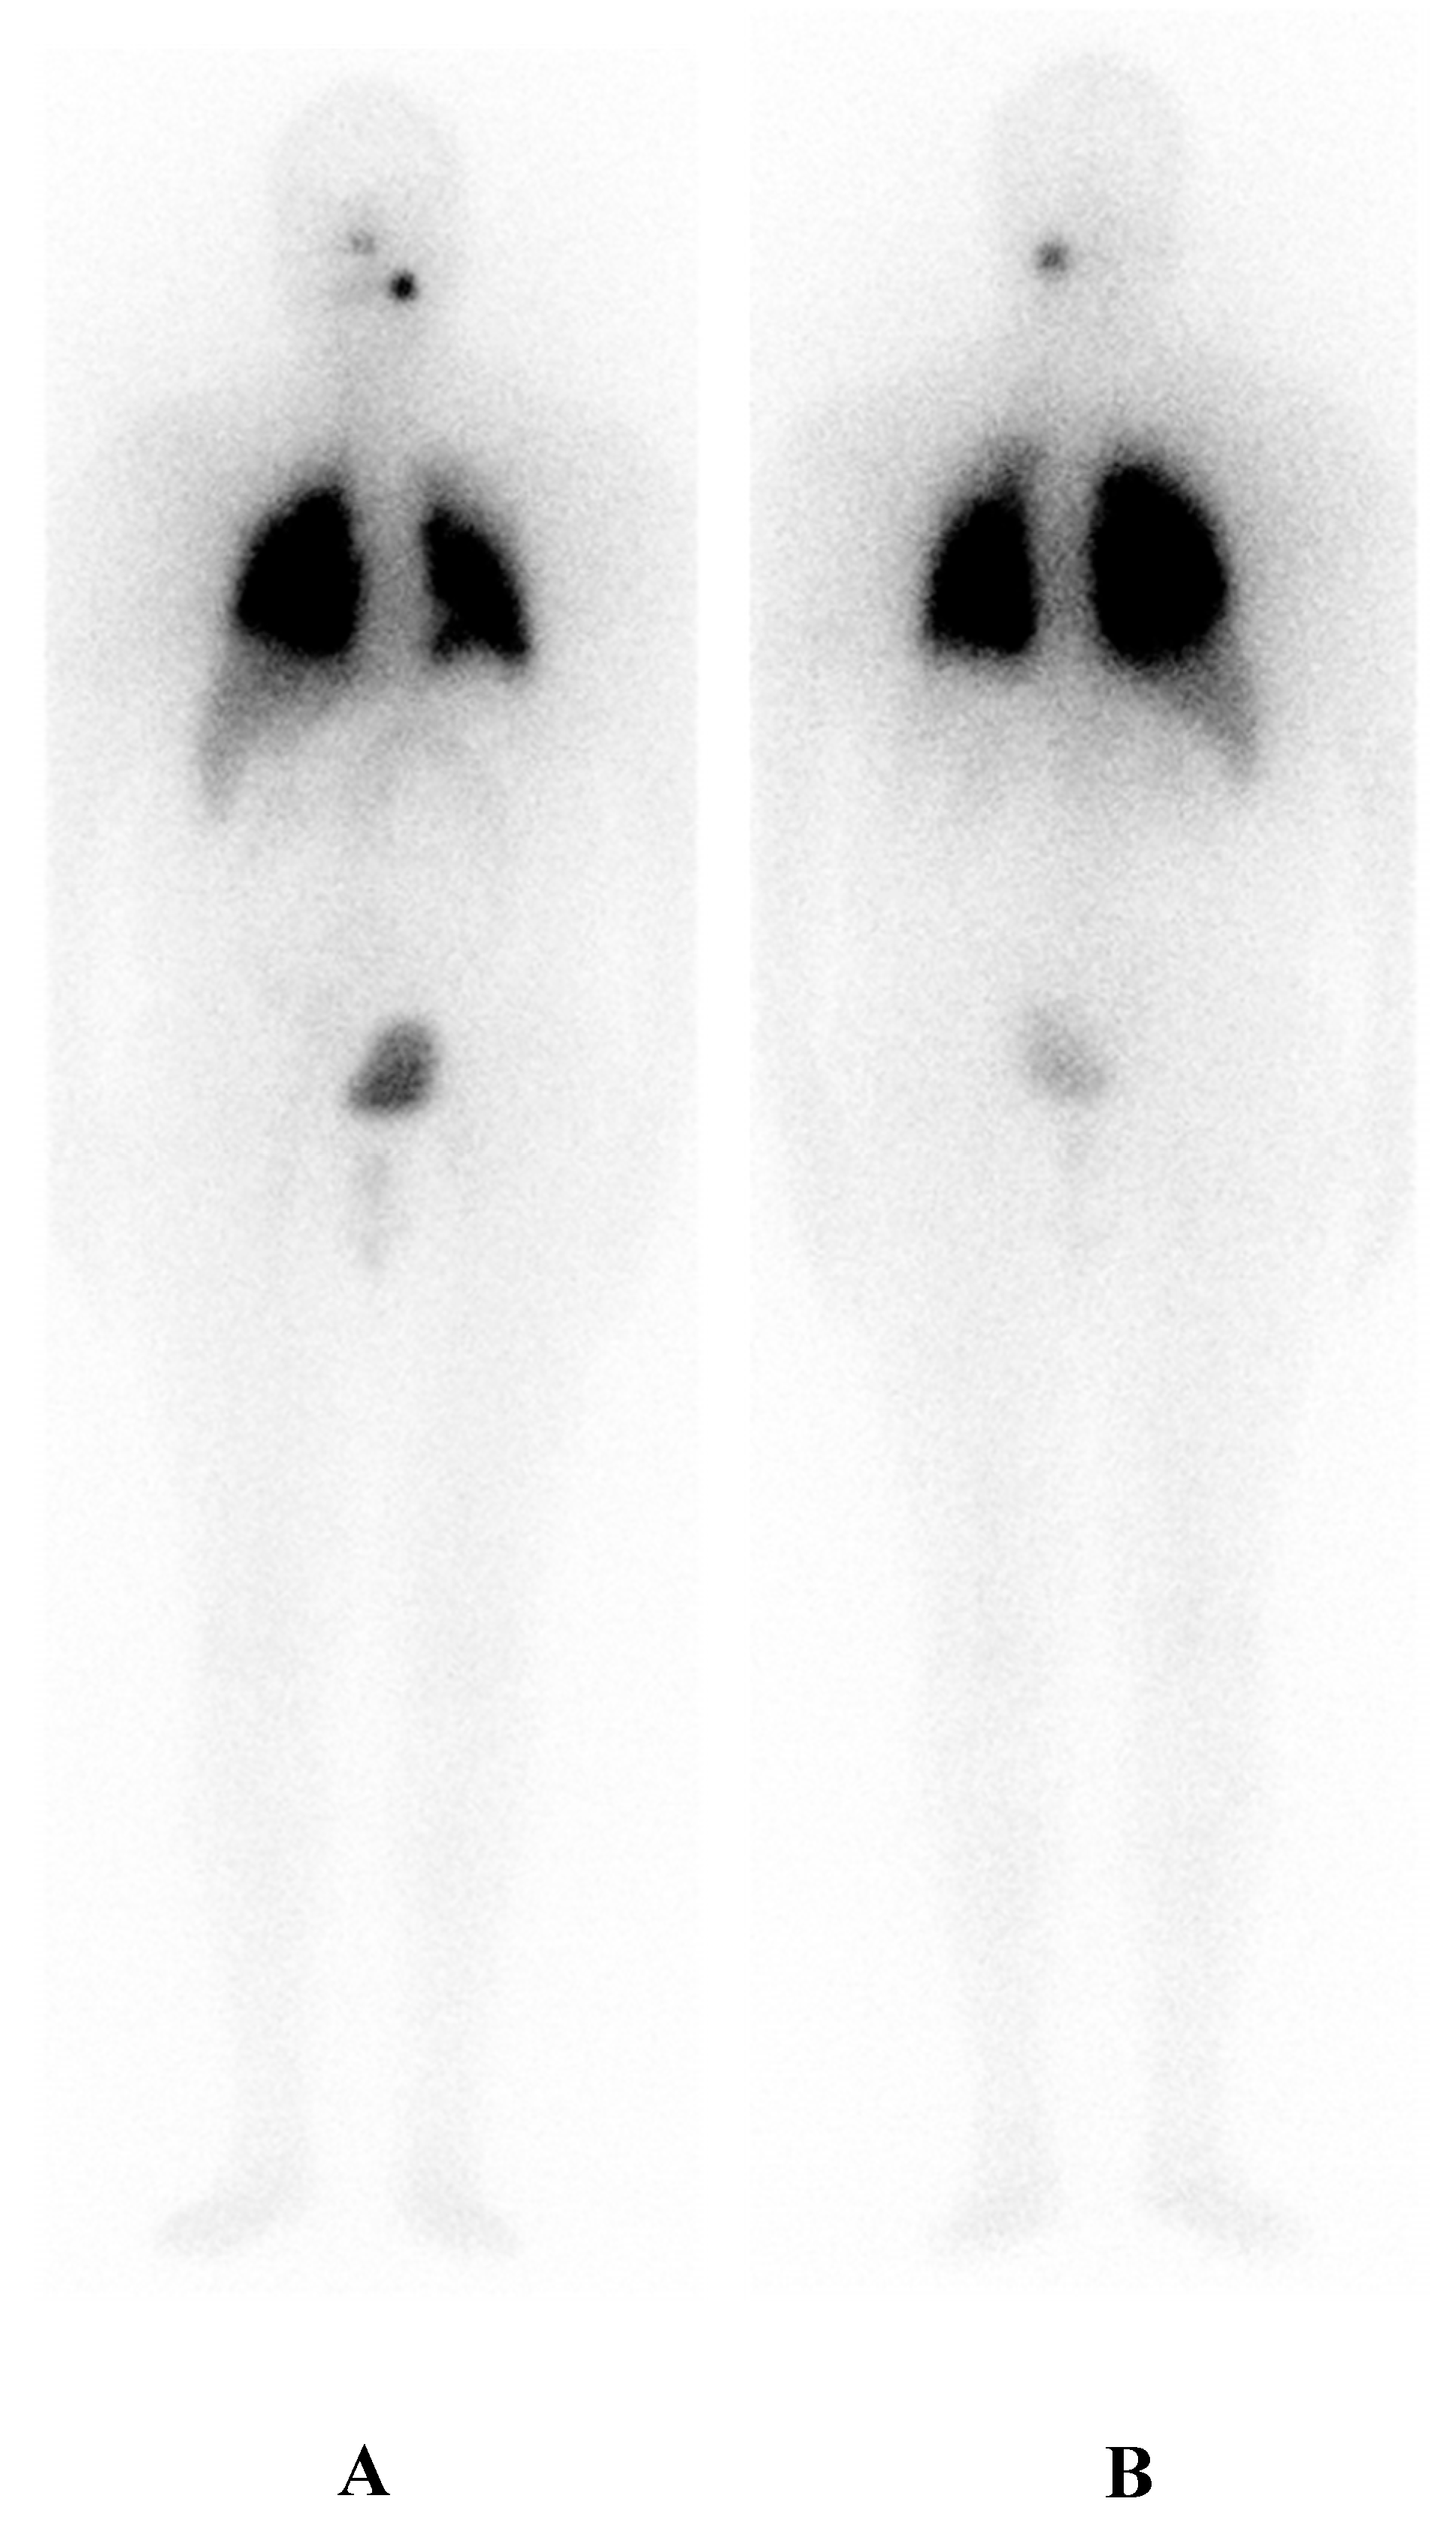

6. A Case of Re-Differentiation